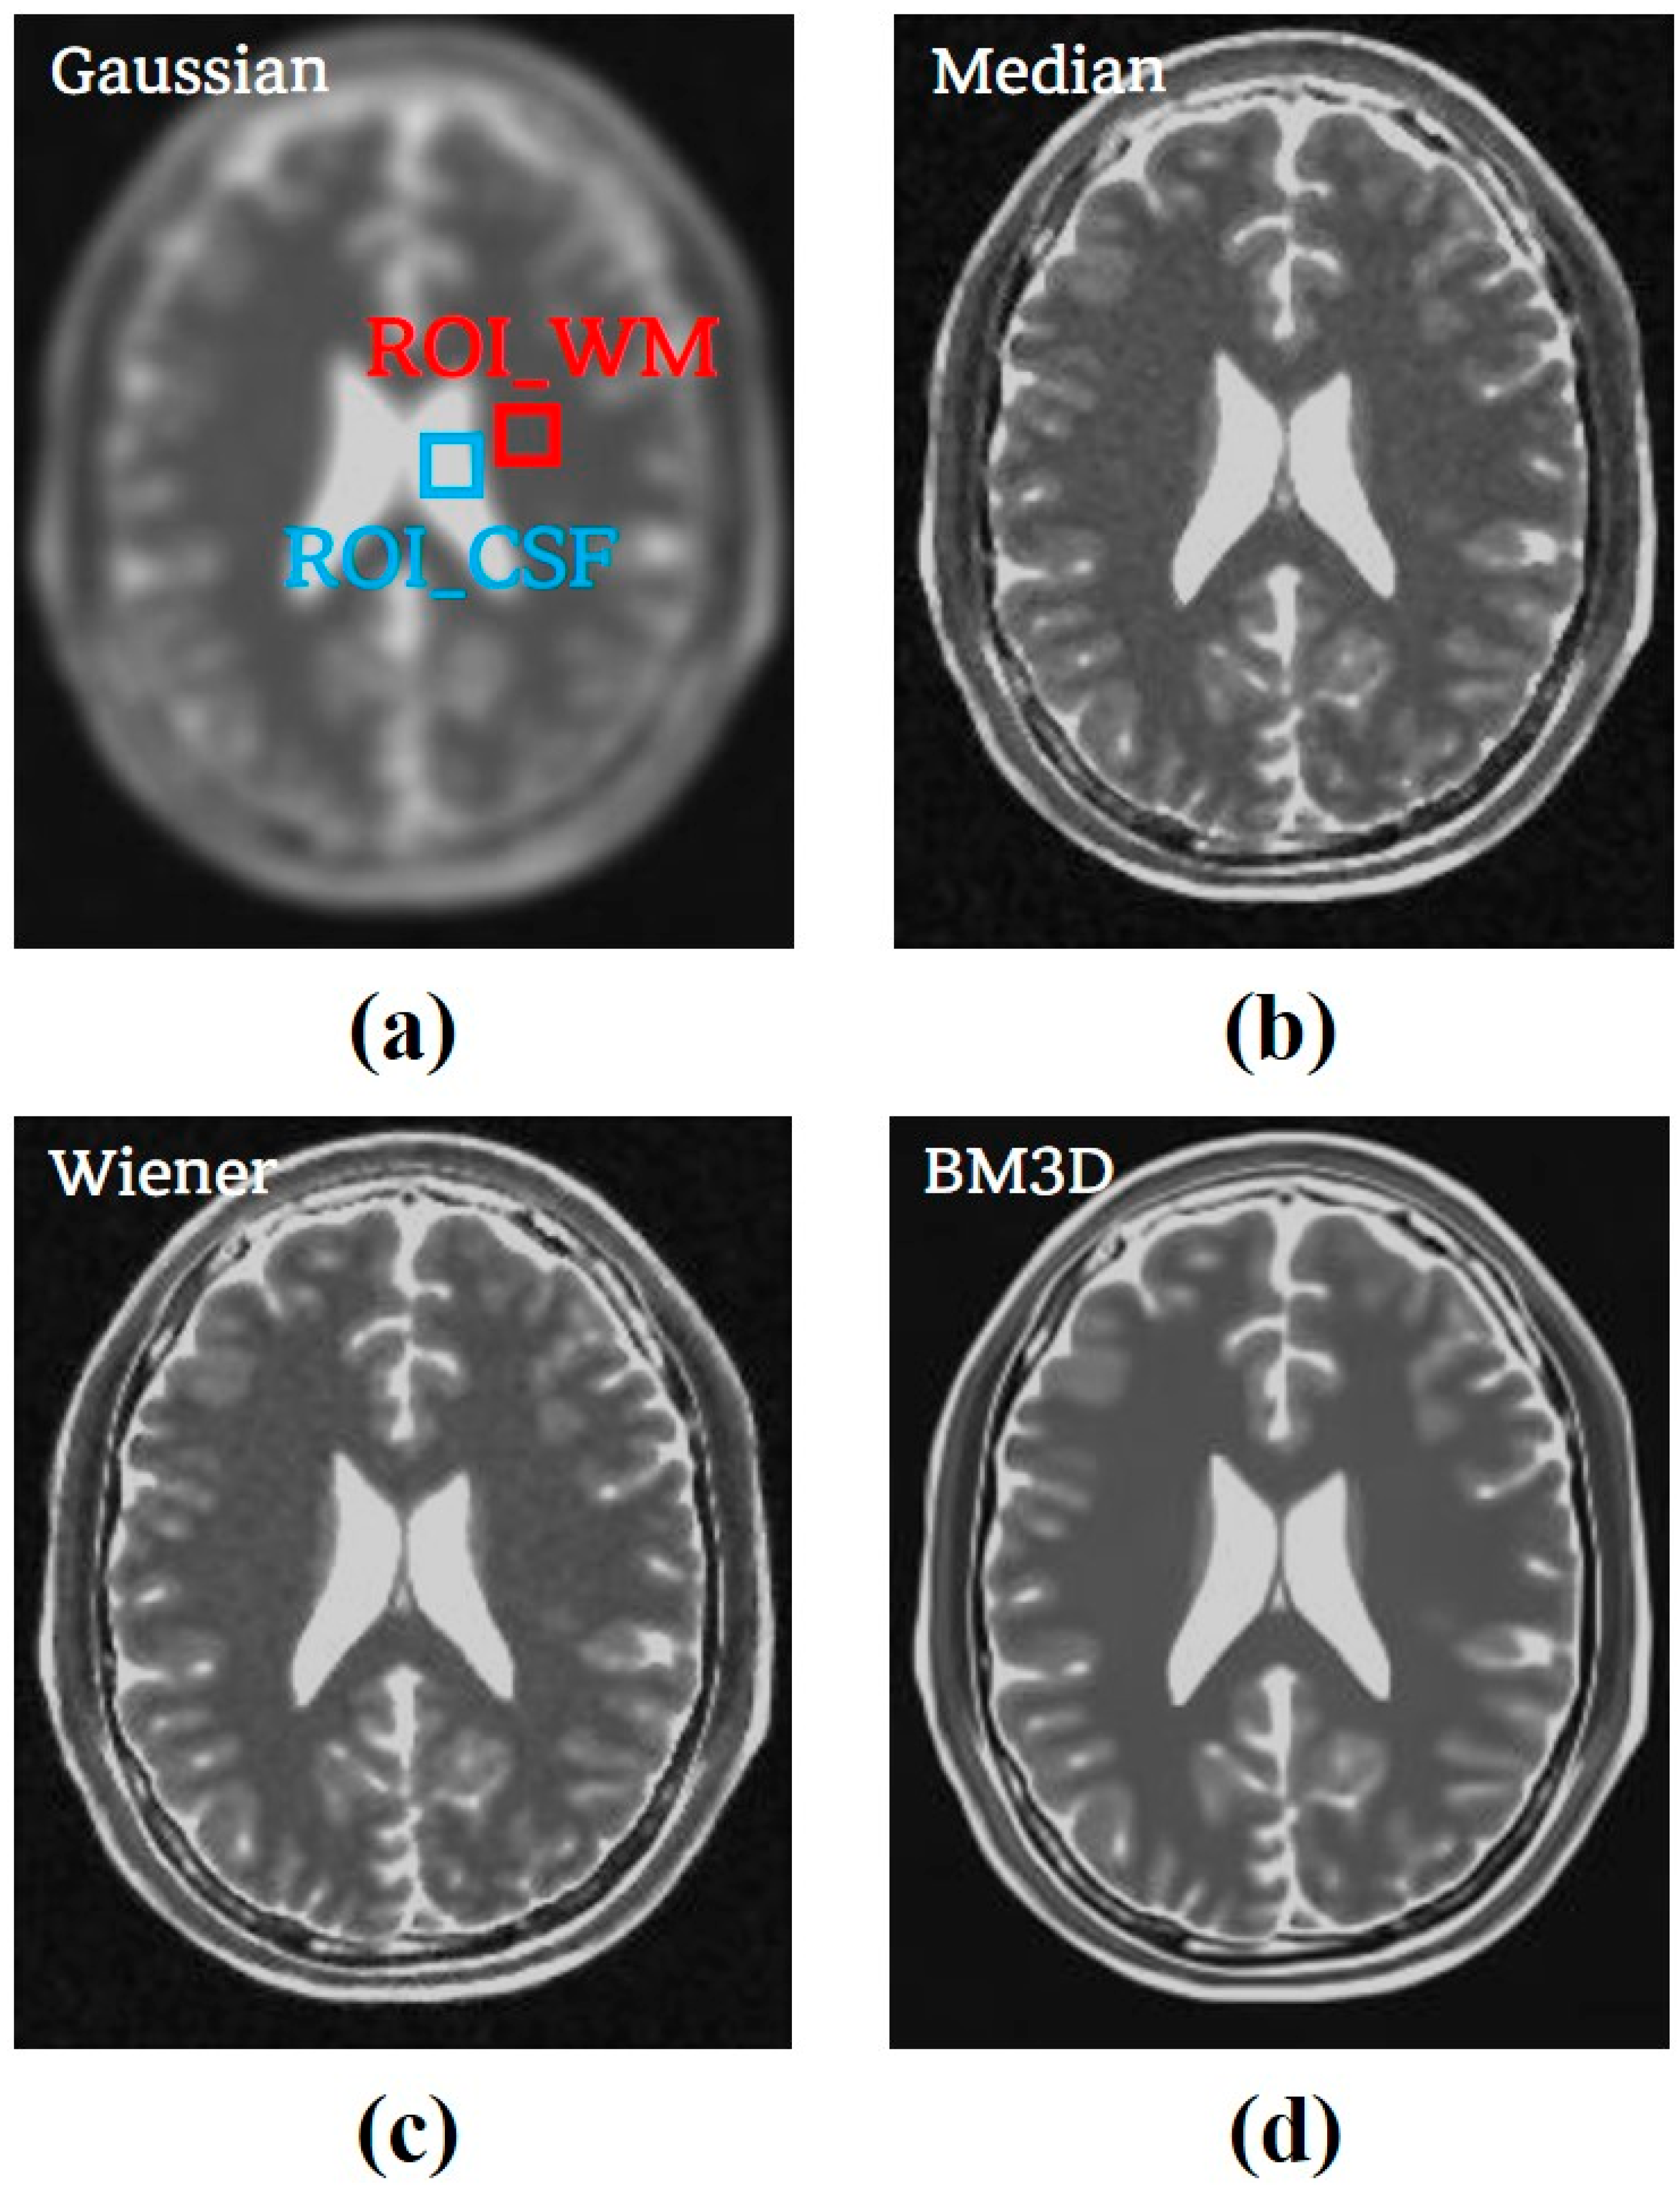

3.2. Clinical Study